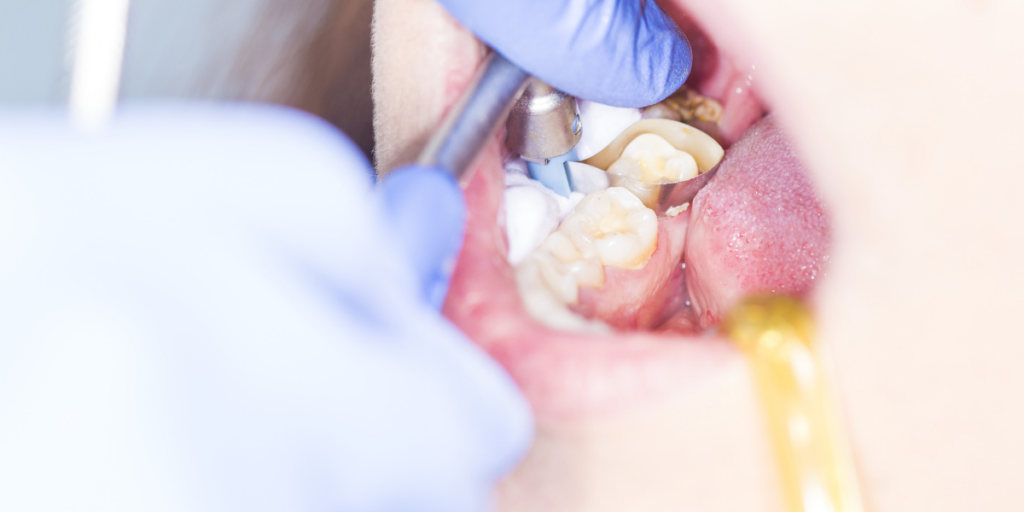

Fillings, Crowns, And Orthodontic Appliances Create “Bacteria Zones”

Edges of fillings and crowns can trap plaque. Orthodontic attachments and aligners can trap plaque, too. If you are in orthodontic treatment, your cleaning plan may need to change.

This is where teamwork helps. Your orthodontist and dental team should support your daily care to prevent plaque buildup around your appliances.

A decay risk assessment considers your cavity history, dietary habits, signs of dry mouth, tooth shape, and enamel strength. It also looks for grinding, gum recession, and the edges of fillings or crowns. If you are doing orthodontic treatment in Clifton, it also checks how cleaning access has changed. This helps a dentist identify the causes of your frequent cavities and choose the right preventive tools for you.

We offer fluoride treatments and prescription options when they are appropriate for your risk level. We also recommend sealants when deep grooves are a problem. Along with these tools, we help you improve oral hygiene in a way that feels realistic, not stressful. The goal is fewer cavities and less tooth decay clifton risk over time.